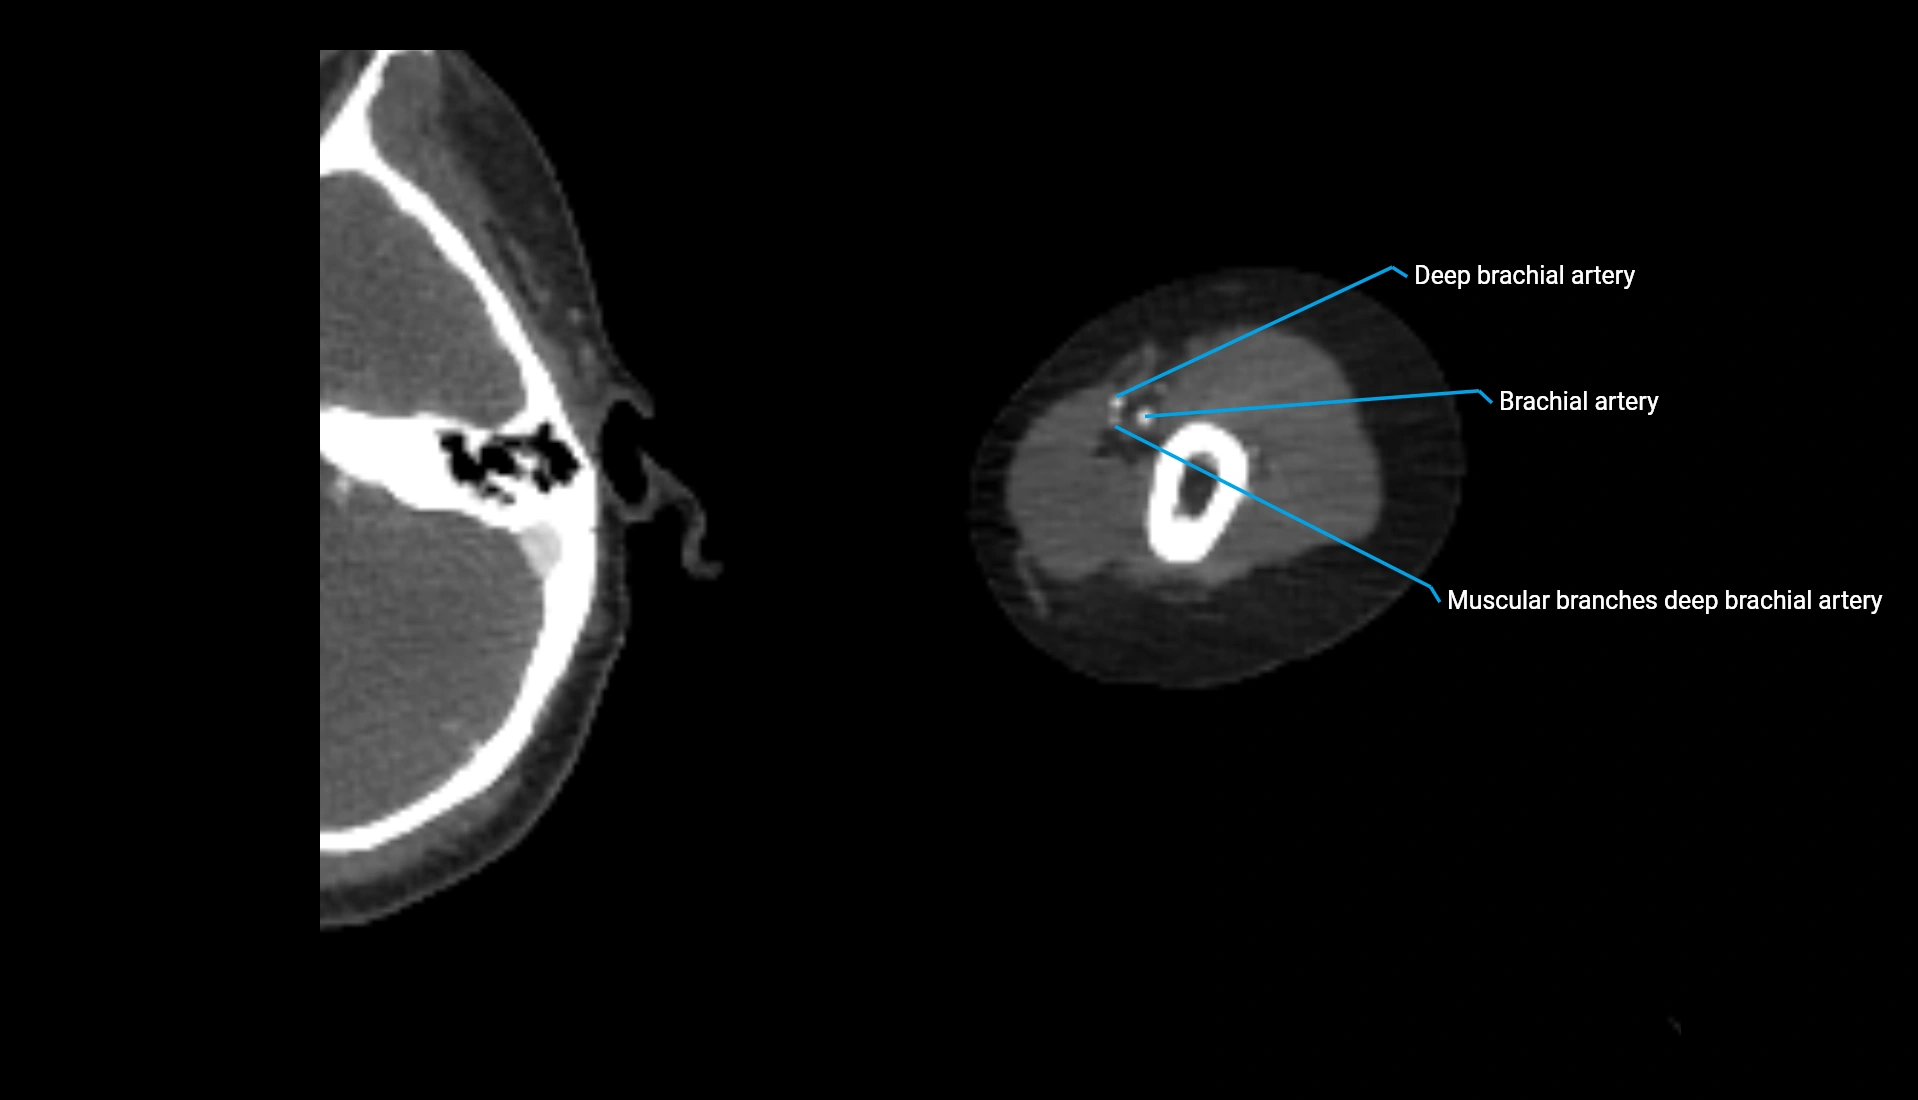

CT Appearance

Non-Contrast CT:

• Cortex: High-density, sharply defined

• Subchondral bone: Dense cancellous matrix

• Articular surface: Smooth concave contour articulating with the capitellum

• Excellent for evaluating bone integrity, alignment, and subtle fractures

Post-Contrast CT:

• Bone: No enhancement

• Joint capsule and synovium: Mild enhancement outlining the joint

• Improves contrast between soft tissues and bony margins

• Useful in detecting subtle joint abnormalities or postoperative changes